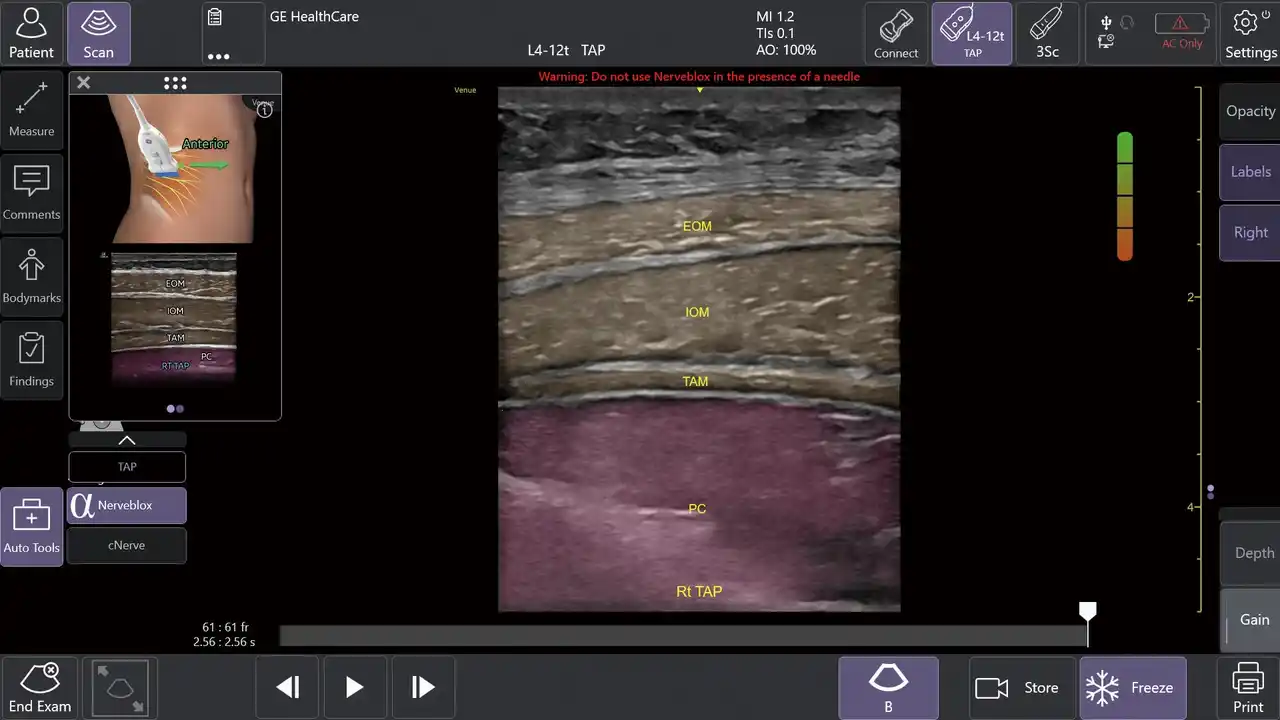

1.AIツール Nerveblox(ナーブブロックス)で神経ブロック手技を効果的にサポート |

AIを用いて開発されたNervebloxは、区域麻酔に用いられる標準的な12種類の神経ブロック部位に対して、神経および周囲組織(筋肉・血管・骨・筋膜など)をリアルタイムに認識し、ハイライト表示する機能です。 |

本機能は、画像クオリティを評価するQuality Meter、プローブの向きをガイドするOrientation表示、組織を色分けするカラーオーバーレイ、解剖構造名を示すアナトミカルラベル、理想的なプローブ位置を提示する模式図ガイド等を備え、走査者のエコー経験レベルに依存しない、より安定した神経描出をサポートします。 |

この機能により、麻酔科、救急科、集中治療科、整形外科など多くの診療科において、神経ブロック時の解剖学的構造の認識や視認性が高まることが期待され、よりスムーズな判断や手技をサポートします。 |

Nervebloxによる神経ブロックのサポート (中央)Anatomical Labeling: 画像上に解剖学的ラベルを略語形式で表示 (右上)Quality Meter:表示画像の品質をリアルタイムで評価して色分け表示 |